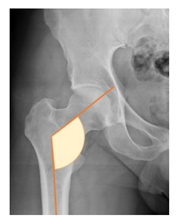

Plain radiographs were evaluated preoperatively and at the most recent follow-up, after appropriate calibration. Positional parameters were assessed according to values guidelines from published literature, as listed in Table 1 [23,24,25,26,27,28,29,30,31]. Femoral stem and acetabular cup osteointegration were quantified according to Engh [32] and Moore scale [33]. Heterotopic ossifications were graded according to the Brooker system [34].

3.4. Radiographic Evaluation

Preoperative and postoperative radiographic data are reported in Table 4. Preoperatively, 18 THR (24.3%) were implanted in skeletally immature children with closed triradiate cartilage (1 ≤ Risser ≤ 3). Radiographic acetabular insufficiency (LCEA < 25° and AI > 13°) was detected in 14 hips (18.9%), while protrusion was present in 3 hips (4.1%) An excessive valgus of the femoral neck was observed in 19 hips (25.7%), while an important varus deformity was present in 7 hips (9.5%).

Postoperative radiographs showed a significant vertical malposition of the cup in 1 case (1.4%), a significant varus stem in 8 cases (10.8%) and a significant valgus stem in 1 case (1.4%). Two patients (2.7%) showed moderate heterotopic bone formation (Brooker ≥ 2), that did not significantly affect the hip motion and symptoms. All those THR that did not undergo revision showed good radiographic osteointegration, with no evidence of implant breakage, radiographic lucencies, bone defects, cup migration, or stem subsidence at the most recent radiographs.

In our experience, implant malposition was the only reason for implant revision. In one case, progressive subsidence was observed in a varus undersized stem, implanted in a boy with Albers–Schömberg disease; in another case, an excessively vertical cup with a 28 mm femoral head caused hip instability and required cup revision.

THR can be a challenging procedure in very young people. The combination of distorted anatomy, small physique, and poor bone stock can impede proper implant placement. Implant sizing may be an issue in these patients. The combination of young age and peculiar conditions such as skeletal dysplasia may require particular attention in preoperative planning and implant selection. Noticeably, we used the smallest size of the cup in 11 hips (15%) and the smallest size of the stem in 14 hips (19%). A meticulous preoperative planning, even using simulation software, [40,41,42] and careful implant selection, sometimes requiring even customized implants [37], is crucial in such conditions, to prevent unpleasant pitfalls during the operation.